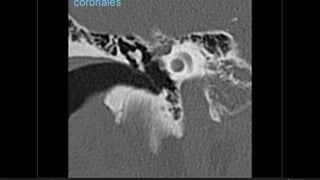

Evaluación Imagenologica

• #49 Izq: Sutura timpanoescamosa, hace mímica de frafctura Centro y derr. Sutura occipitomastoidea

• #50 IZQ: Sutura esfenoescamoosa,, lateral al foarmen espinoso(punta de flecha) DDER: sutura esfenopetrosa: foramen oval(astericos), trompa eustaqui (punat negra)